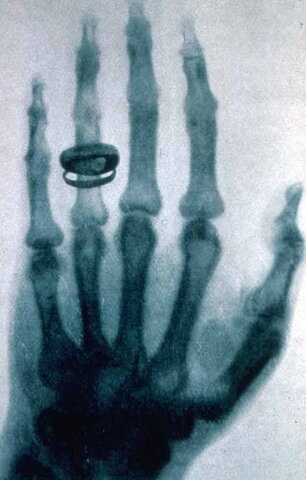

Primera Radiografia

Roentgen publico la primera imagen de rayos X médica, la cual fue una imagen de la mano de su esposa.